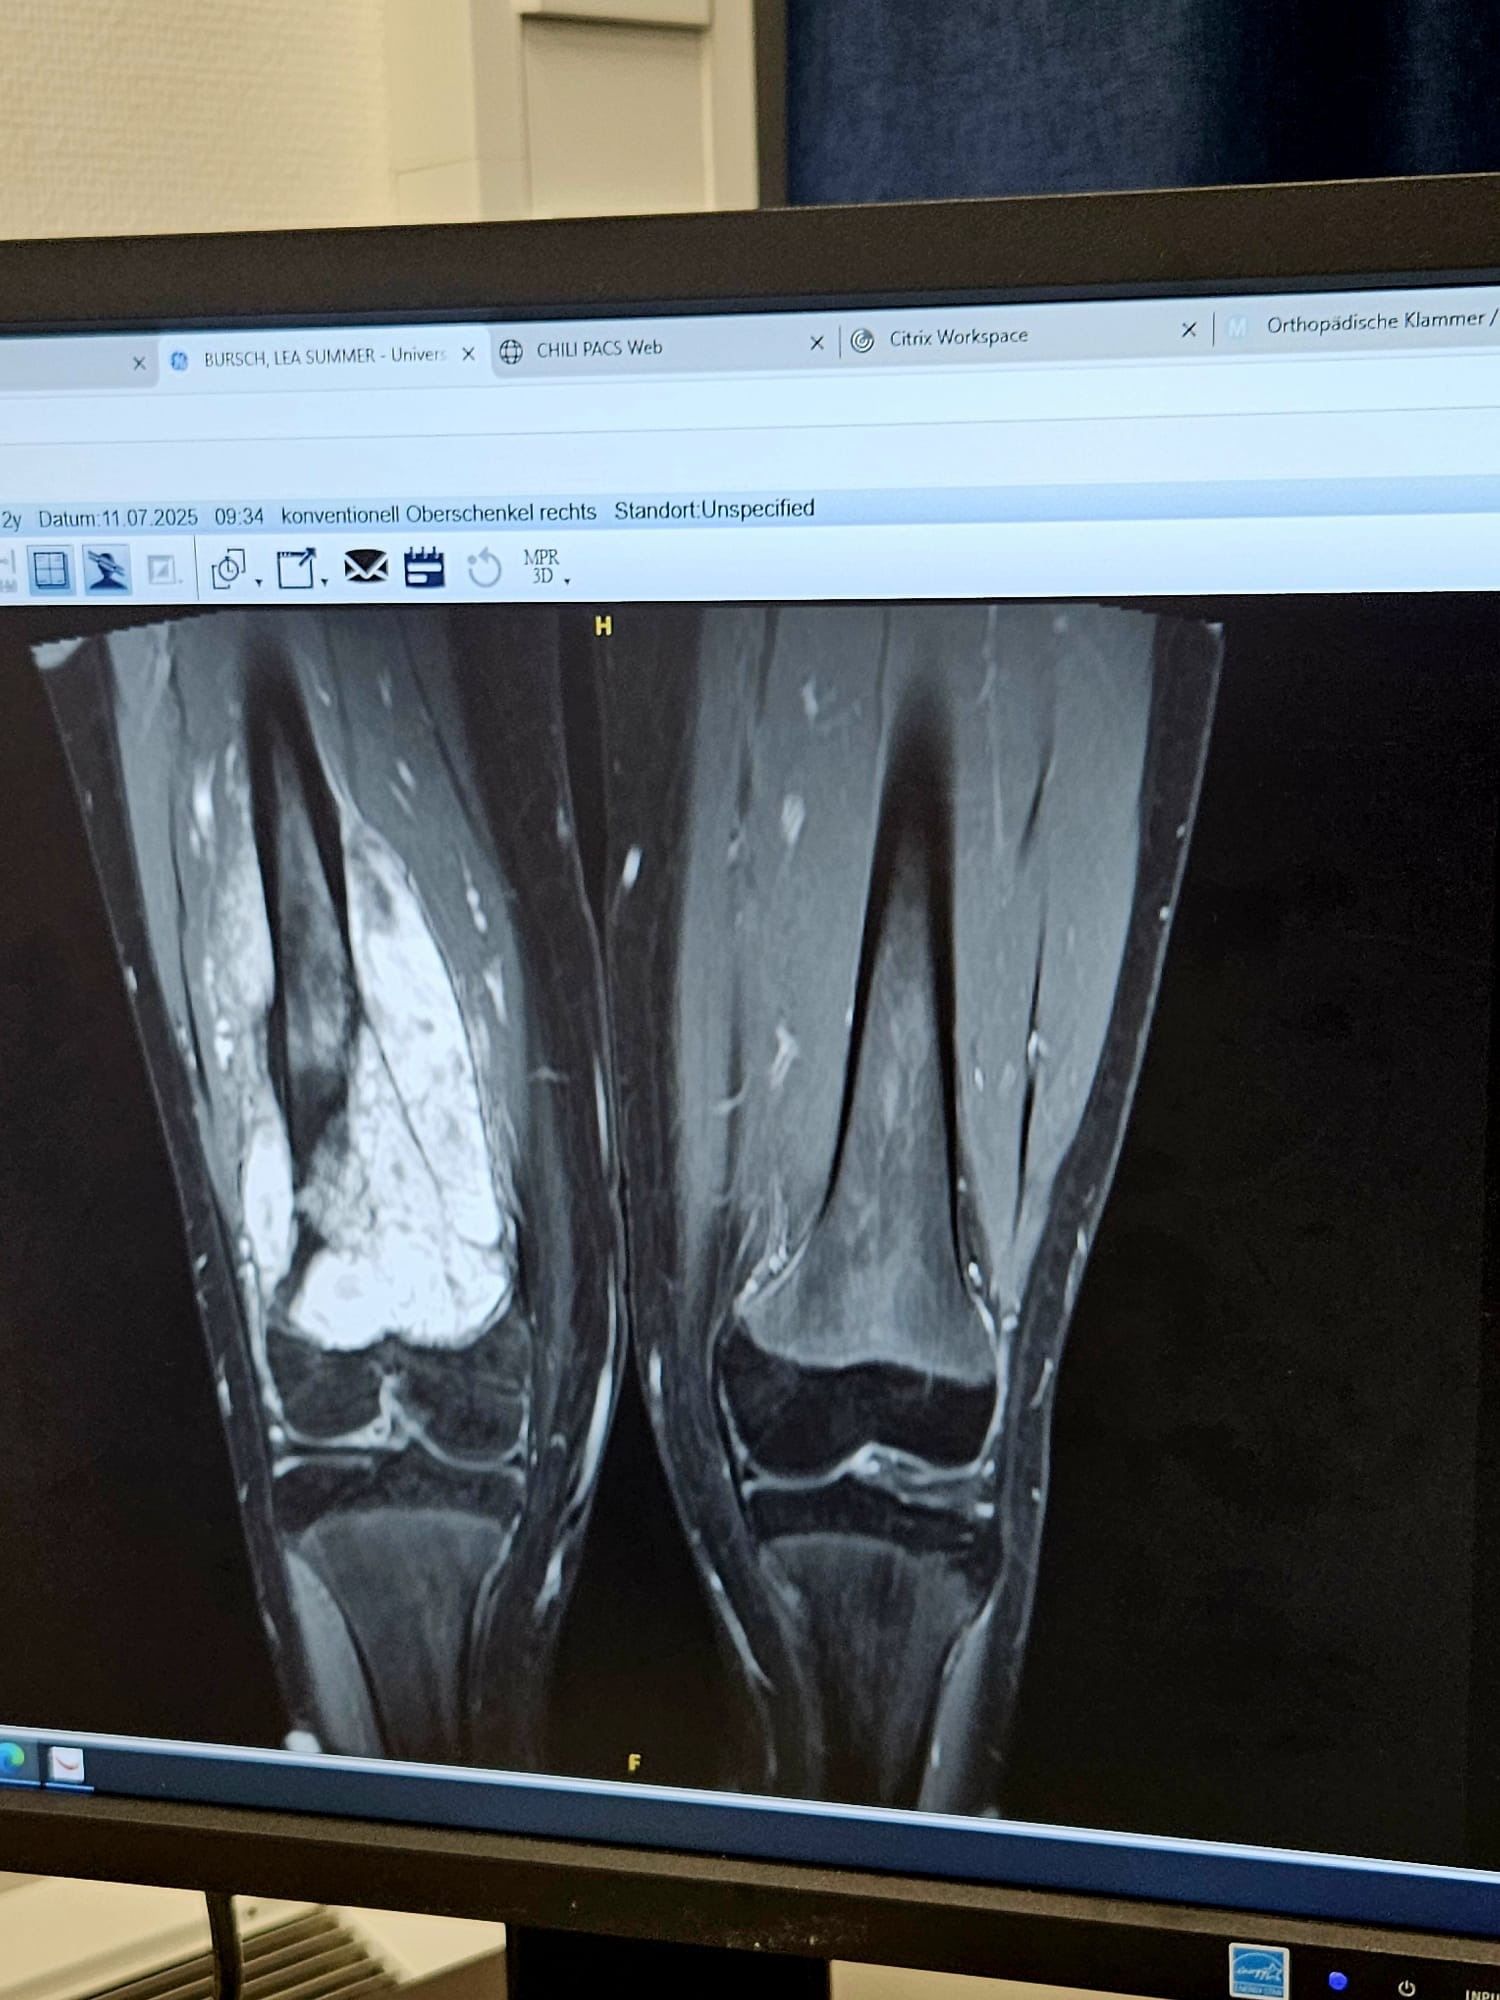

im Januar 2025 erhielten wir die erschütternde Nachricht: Unsere geliebte Tochter Lea, gerade einmal 12 Jahre alt, leidet an bösartigem Knochenkrebs. Seitdem kämpft sie mit einem Mut und einer Stärke, die uns – ihre Mutter Jennyfer, ihren Vater Sebastian und ihre 13-jährige Schwester Nina – jeden Tag aufs Neue inspiriert. Doch dieser Kampf fordert nicht nur Lea, sondern unsere ganze Familie, und wir brauchen Ihre Hilfe, um ihr die bestmögliche Unterstützung zu geben.

Lea hat bereits neun Chemotherapien durchgestanden, jede einzelne ein schwerer Schritt auf ihrem Weg. Im August 2025 wurde sie operiert, wobei 22 cm ihres Oberschenkelknochens entfernt und durch eine Prothese ersetzt wurden. Die Operation verlief erfolgreich, doch Lea’s Reise ist noch nicht zu Ende: Im September 2025 beginnt ihre zehnte Chemotherapie, und insgesamt sind noch fünf weitere Chemotherapien geplant. Neben der schulmedizinischen Behandlung setzen wir auf Heilpraktiker und Mikronährstoffe, die gute Ergebnisse zeigen, aber leider nicht von der Krankenkasse übernommen werden. Die hohen Kosten für diese Behandlungen, die vielen Fahrten zum Krankenhaus und die Gehaltseinbußen durch Krankengeld belasten uns finanziell stark.